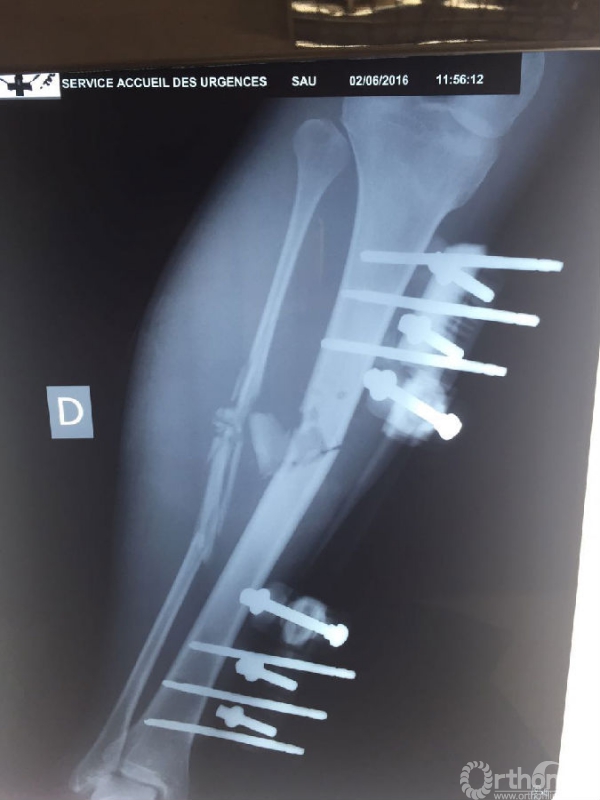

战士李涛,因31日的爆炸袭击导致左大腿及右小腿严重损伤。塞方初期已行右小腿开放性骨折清创外固定架固定及左大腿清创转移皮瓣修复术。杨润功教授亲自给伤员查体换药,仔细观察伤口渗出及皮瓣愈合情况,重新调整了外固定架,叮嘱塞方医护人员加强换药观察,并向伤员及陪护人员详细交代了后期功能康复细节要点。现李涛生命体征平稳,伤口渗出已明显减少。

李涛右小腿X线片